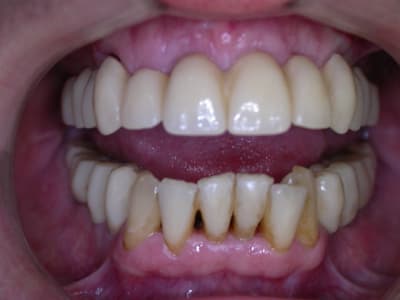

21 jours post-op

Oui patient très heureux même avec une petite "surcharge" implantaire selon certains ;-)

comme quoi , finalement, même si nous ne sommes pas d'accord sur la façon d'y arriver, seul le résultat compte.

le patient est content.